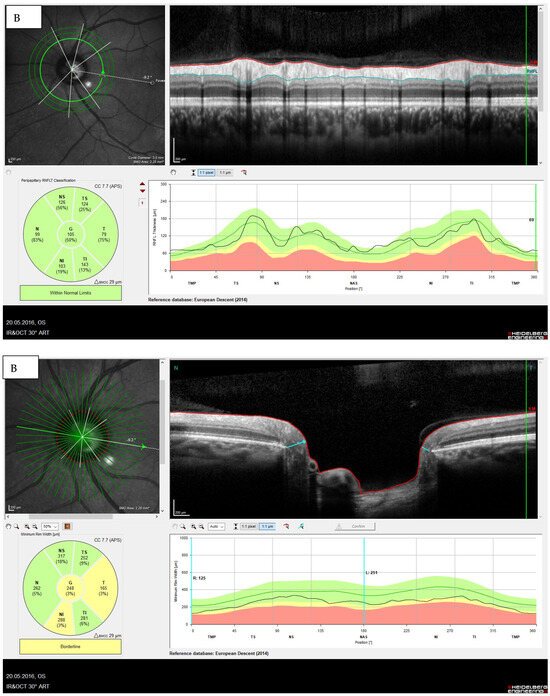

The Minimum Rim Width (MRW)

- Influence of the optic disc size on the MRW:

The Retinal Nerve Fiber Layer (RNFL)

- Influence of refraction on the RNFL:

- Influence of ethnicity: